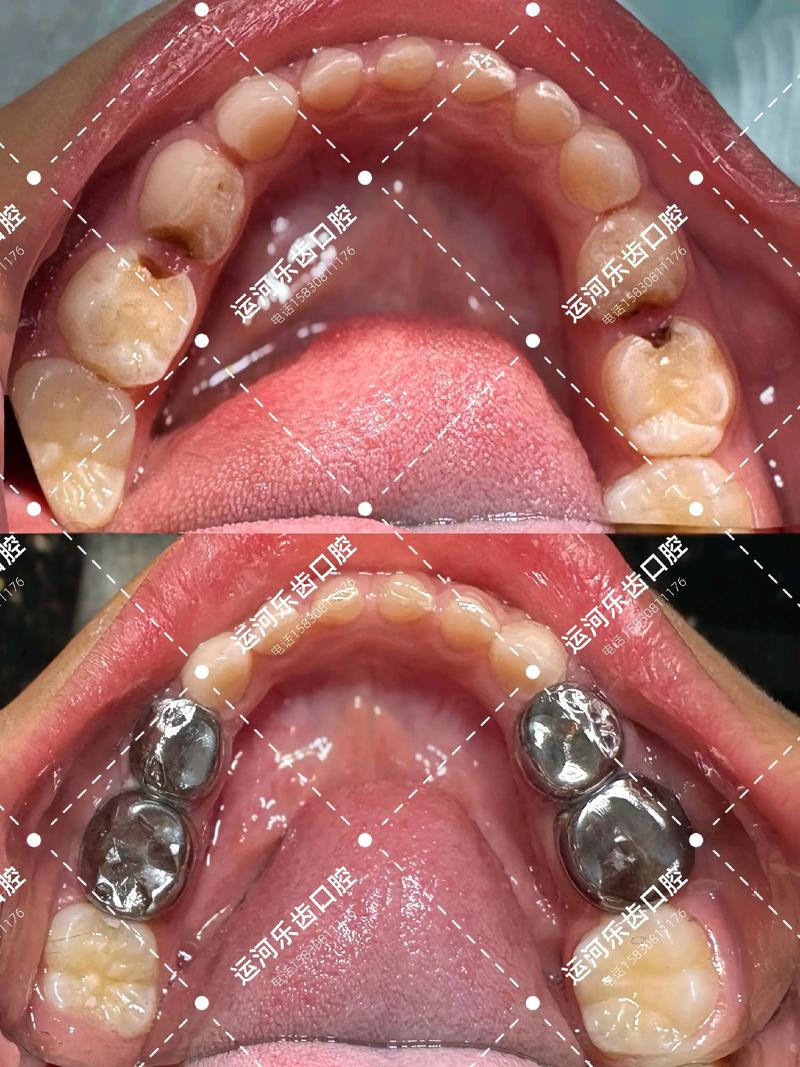

在儿童口腔治疗中,预成冠的作用尤为突出,儿童乳牙牙体组织较薄,龋坏进展迅速,一旦发生大面积缺损,易引发牙髓炎或根尖周炎,预成冠能够快速恢复牙齿外形,避免因过早失牙导致的错颌畸形,对于深龋乳磨牙,预成冠可覆盖剩余牙体,隔绝外界刺激,同时维持乳牙间隙直至恒牙萌出,预成冠的金属材质具有较高的强度,能承受儿童日常咀嚼力,且边缘密合性好,减少了二次龋的风险,近年来,美观性改良的预成冠(如树脂预成冠或陶瓷预成冠)也逐渐普及,满足了前牙修复的美学需求。

对于恒牙而言,预成冠常用于以下场景:一是作为年轻恒牙的暂时性修复,因年轻恒牙牙根尚未发育完成,预成冠可保护牙髓并维持牙齿功能;二是作为大面积龋坏或外伤后的永久性修复,尤其是后牙区,预成冠的咬合面设计能分散咀嚼力,降低折裂风险;三是作为桩核冠的基础,为后续全冠修复提供固位支持,值得注意的是,恒牙预成冠的材料选择更为多样,包括全瓷、金属烤瓷等,可根据患者对美观和强度的需求进行个性化定制。